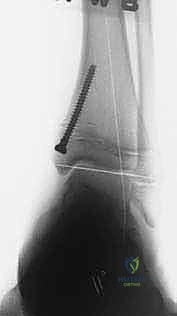

الخطوة الرابعة: تثبيت الشريحة (8-Plate)

بمهارة فائقة، يقوم الدكتور هطيف بوضع الشريحة المعدنية المصنوعة من التيتانيوم الطبي النقي فوق مركز النمو. يتم تثبيت الشريحة باستخدام مسمارين صغيرين؛ أحدهما فوق خط النمو والآخر تحته. هذه المسامير لا تخترق مركز النمو نفسه، مما يضمن عدم تدميره.

- الأشهر من 1 إلى 6: هذه هي مرحلة "السحر الطبي". خلال هذه الأشهر، ومع نمو الطفل، يبدأ الانحراف بالتلاشي تدريجياً. تتم جدولة زيارات دورية لعيادة الدكتور هطيف لإجراء أشعة سينية ومراقبة تقدم التصحيح.

- إزالة الشريحة: بمجرد أن يستقيم الكاحل ويصل إلى الزاوية الطبيعية المثالية (غالباً بعد 6 إلى 12 شهراً)، يتم إجراء عملية جراحية صغرى وسريعة جداً لإزالة الشريحة والمسامير، ليُترك الطفل بقدم سليمة ومفصل طبيعي تماماً.